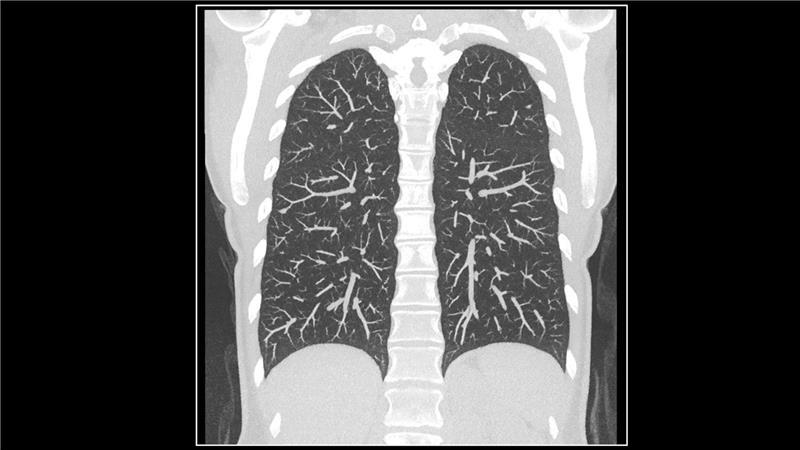

Unter dem Motto „Radiologie leben – mehr als High-End-Technologie“ richten wir unseren diesjährigen Auftritt verstärkt auf Themen rund um unseren ausgezeichneten Service, die ganzheitliche Betrachtung klinischer Pfade und natürlich Innovationen im Bereich der Radiologie aus.